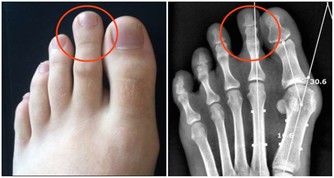

2、膝部及關節疼痛